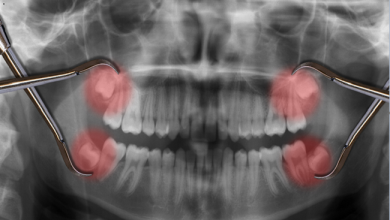

ضرس ينمو في مكان غريب بجسم شاب أميركي

في مفاجأة غريبة لمريض أميركي نما سن له في أنفه بعد شعوره باحتقان شديد، ما استدعى ذهابه للطبيب الذي صدمه…